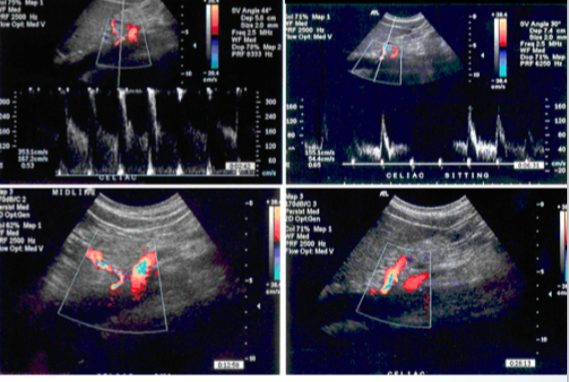

Pt with abdominal pain after eating has arterial duplex US images shown below. Most likely diagnosis?

*Note that left panel images were taken from supine position and right panel from sitting position.

median arcuate ligament syndrome